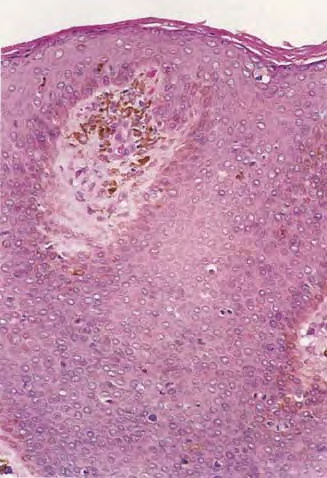

Histopathologically, the epidermis is usually hyperplastic with atypia, disordered maturation, scattered mitotic figures, and dyskeratotic keratinocytes.

The epidermis displays full-thickness atypia, including in the intraepidermal portions of the adnexal structures . Involvement reaches from the stratum corneum down through the basal cell layer, although the basement membrane remains intact. Characteristically, parakeratosis and hyperkeratosis are present, as is acanthosis, with complete disorganization of the epidermal architecture. At times the hyperkeratosis and parakeratosis are so pronounced that a cutaneous horn is present. Throughout the epidermis are numerous atypical, pleomorphic, hyperchromatic keratinocytes. These cells are sometimes vacuolated and have a prominent pale-staining cytoplasm, reminiscent of the cells in Paget disease. These cells show loss of maturation and polarity, in addition to numerous mitotic figures. Individually keratinized cells with large, rounded, eosinophilic cytoplasm and hyperchromatic nuclei can be found in the epidermis, as can multinucleated cells. These atypical cells also are seen throughout the pilosebaceous units, within the acrotrichia, follicular infundibula, and sebaceous glands. The upper dermis is typically infiltrated by numerous cells associated with chronic inflammation, including lymphocytes, plasma cells, and histiocytes.